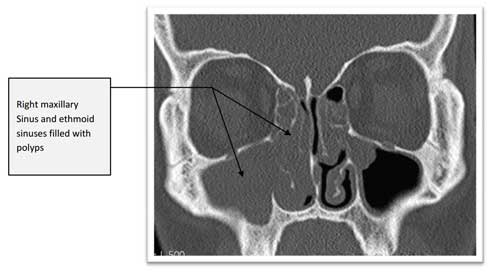

nasal sinuses CT of nasal polyps CT of normal sinuses CT after removal of polyps Removing nasal polyps is actually quite straightforward, however reducing the chances of them returning is quite a lot harder. Generally ‘polypectomy’ can just mean removing the bulk of the polyps allowing improved breathing, but there is a significant chance that they will grow back even with steroid sprays. Clearing out polyps from their ‘roots’ and opening up these areas so steroid sprays prevent polyps from growing back has been shown to reduce the chance of the polyps growing back. Avoiding multiple operations is something Mr Vik Veer is very keen on, and he will advise you on the various options for nasal polyps. The most important thing to remember is that the polypectomy operation does not ‘cure’ polyps, it merely cleans them out temporarily. The vast majority of patients will need steroid sprays to avoid another operation again. Prof Vik Veer uses medication before any procedure to try and avoid surgery if at all possible, and there are a number of therapies that may help with nasal polyps.